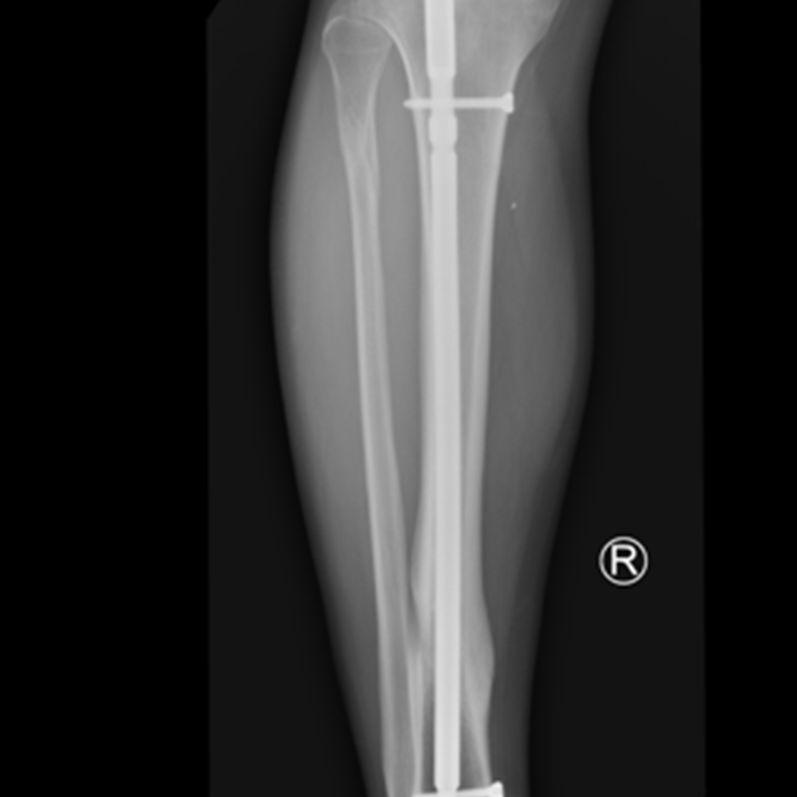

Przykład takiego zespolenia obrazuje zdjęcie 1.

Zdjęcie 2.

Zdjęcia przedstawiają etapy gojenia (zrostu wtórnego), złamania kości piszczelowej zespolonej gwoździem śródszpikowym, od złamania do uzyskania zrostu.